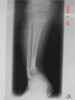

Pre Op

Ankle deformity and shortening in a 7year old child

X-Rays